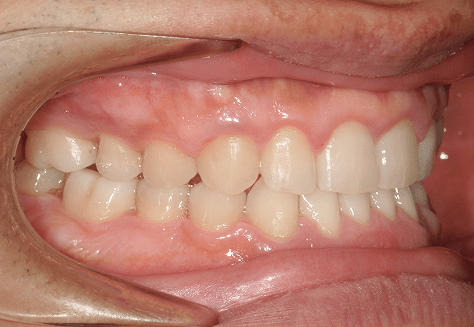

M.U

治療前

治療後

主訴

下の歯が特にガタガタなのが気になる。上の前歯が1本反対になっている。

診断

下顎前突・叢生・反対咬合

年齢/性別

20代/男性

抜歯部位

非抜歯

使用装置

上下インビザライン(PBM使用)

保定装置

ビベラリテーナー

料金

初回資料採得・・・・・・・30,000円

診断料・・・・・・・・・・33,000円

動的治療終了時資料採得・・5,500円 -

基本料金

950,000円

診察料金

5,500円×16回

治療期間

1年7カ月